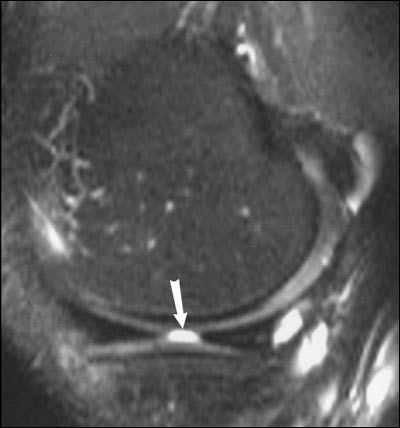

| Twenty-eight-year-old man with knee pain after surgery. Patient had surgically proven meniscal radial tear. Above, proton density-weighted sagittal MR image (TR/TE, 1,800/12) shows findings consistent with meniscal radial tear (arrow). Below, T2-weighted sagittal MR image (3,950/51) shows linear radial tear (arrow). Magee T, Shapiro M, Williams D, "Prevalence of Meniscal Radial Tears of the Knee Revealed by MRI After Surgery," (AJR 2004, Vol. 182, pp. 931-936). |